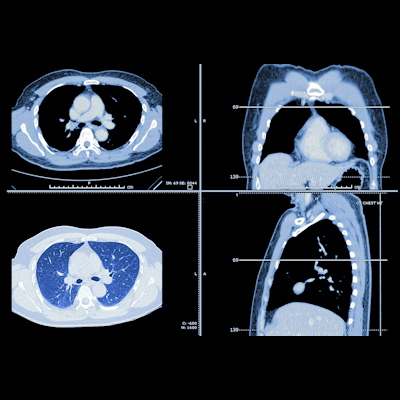

Adding deep learning to CT imaging to assess changes in subcutaneous adipose tissue (SAT) over time could help predict outcomes among individuals vulnerable to lung cancer, according to research presented at the recent RSNA meeting.

A German team developed a deep learning model for automatic 3D quantification of adipose tissue on low-dose chest CT and assessed any associations between this tissue and mortality among a population of heavy smokers at high risk of lung cancer who participated in screening. What did they discover? Check out our featured article to find out.

Finally, we're highlighting a large study published in November that underscored the value of low-dose CT (LDCT) for diagnosing early-stage lung cancer -- which translates to a 20-year survival rate of 81%.